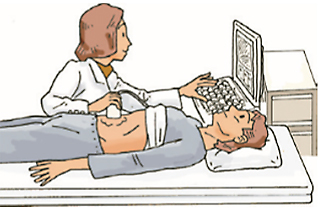

超音波検査

超音波検査では、陰嚢の表面に超音波を当てて臓器から返ってくる反射の様子を画像にすることで精巣の内部を観察します。

多くの場合、超音波検査によって精巣内の腫瘍は推測可能です。血液の流れがわかるカラードップラー超音波検査では、腫瘍の血流についても調べることができます。しかし、病理組織学的な診断が最終診断となります。